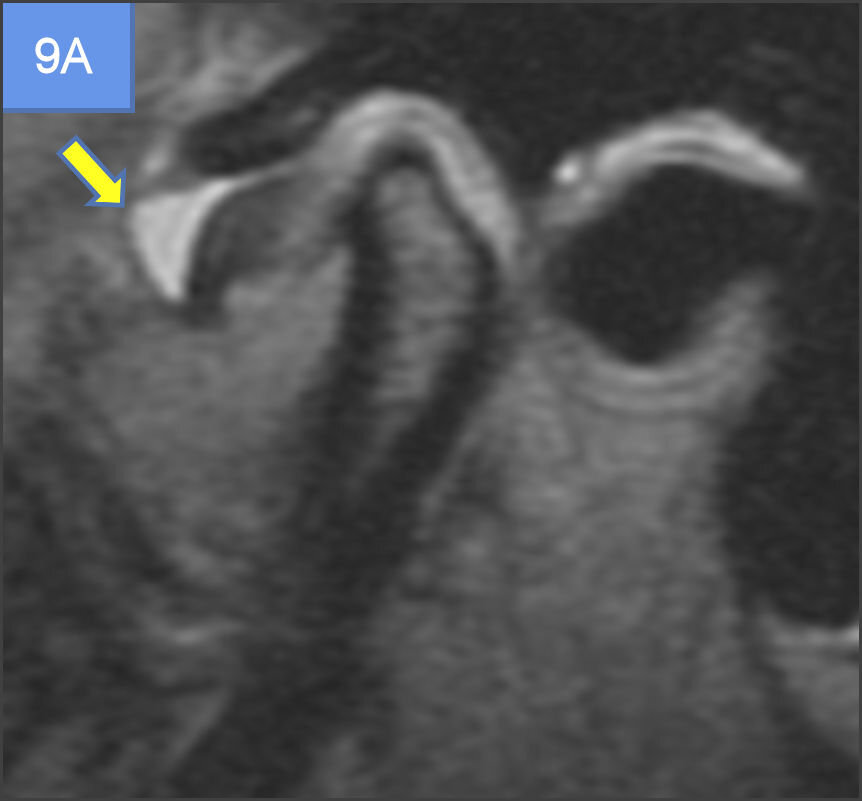

A study done by K Ikeda et al30 which showed that, in case of partial disc displacement(PDD), the condyles were displaced posteriorly in the fossae with a mean anterior space of 2.7 ± 0.5 mm (normal 1.3 ± 0.2 mm) and a posterior space of 1.8 ± 0.4 mm (normal 2.1 ± 0.3 mm). In total disc displacement without reduction (TDDWR), the condyles were displaced not only posteriorly as observed in PDD, but also vertically with a reduced superior space of 1.9 ± 0.4 mm (normal 2.5 ± 0.5 mm). Also, the mean posterior space in case of total disc displacement was further reduced. In the present study, partial displacement (identified by position of posterior band) of disc was more in group III followed by group II, while complete displacement was seen more in Group II (See Figures 6, 7A and 7B) and so was the disc non-reducibility and deformity in open and closed mouth. The inconsistencies in the result might be due to unequal number of joints in each group.

A study done by Emshoff et al,38 revealed, significant relationship between the presence of TMJ bone marrow edema and the MR diagnoses of TMJ internal derangement particularly, disc displacement without reduction and effusion. Although, TMJ internal derangement alone was not always associated with bone marrow edema, it can be present without the evidence of bone marrow edema as well. The association between TMJ bone marrow edema and effusion may be supported by the fact, that the bone marrow abnormalities represent a response to an increased intra-articular pressure in conditions such as synovitis and effusion.39,40 In the present study, Group II followed by Group III (See Figure 8, Figures 9A & 9B) demonstrated highest frequency of bone marrow edema, non-reducibility of disc in open mouth and effusion and hence, was consistent with the findings of previous studies.